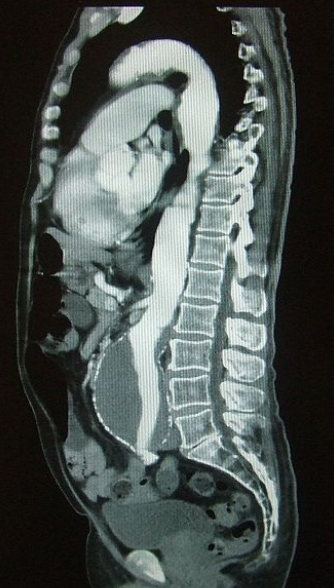

How do you investigate a suspected AAA (not ruptured)?

- US

Transfer to local vascular unit: if unstable immediate theatre for open surgical repair, if stable CT angiogram to determine if suitable for endovascular repair

AAA most commonly infrarenal